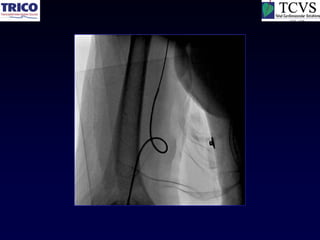

Simple loop

More

challenging

loop

Most

“Downsize the Catheter”